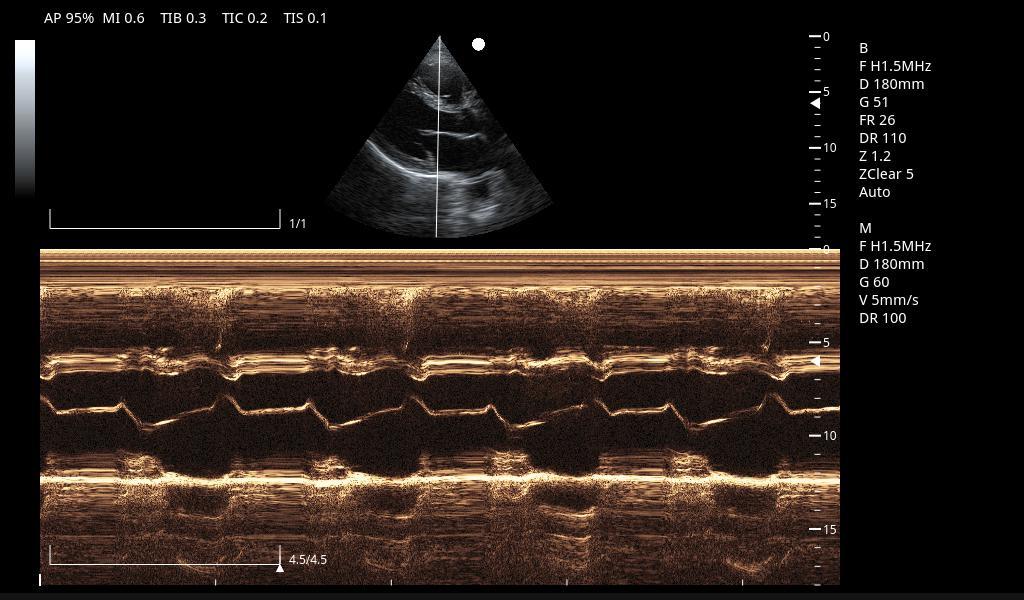

Excelentes imágenes clínicas

|

|

|

|

|

|